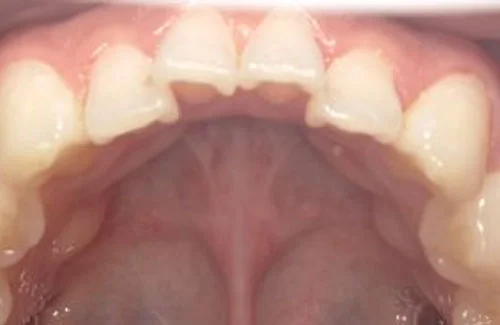

- 症例1

治療期間 4カ月

治療費 23.1万円(月額1,925円~)

※上顎前歯部、下顎前歯部の叢生をマウスピース型矯正装置で改善したケース。矯正治療上のリスクとして、治療中の虫歯、歯根吸収、歯肉炎 ・歯周炎の発生などが考えられる。